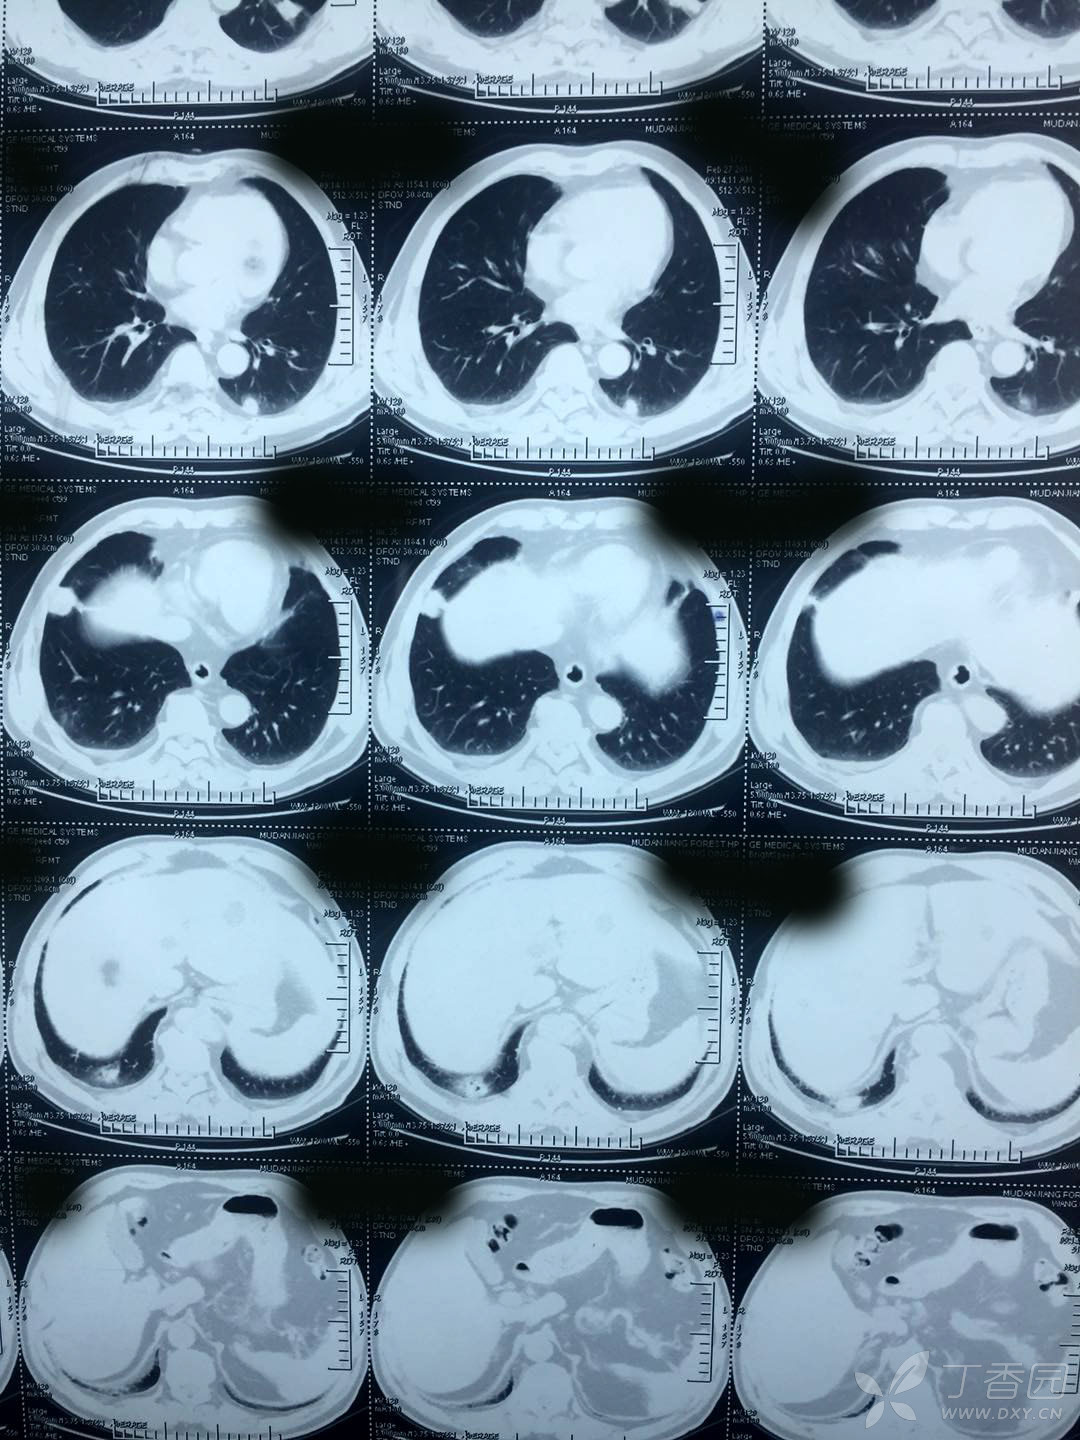

双肺多发结节 穿刺后胸腔积液 [病例帖]

mmexport1536226997170.jpg